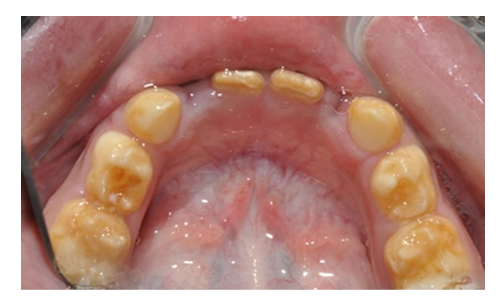

Prema spoljašnjem izgledu oštećenja gleđi nepravilnosti mogu da budu samo u obliku promene boje(bela, žućkasta) sto se naziva stručno HIPOMATURACIJA(bele mrlje-videti na kraju teksta), ili pravih defekata nepravilnog oblika što se naziva HIPOPLAZIJA.(slika 1.)

Oblici razvojinih nepravilnosti gleđi: a) HIPOMATURACIJA (desno) b) HIPOPLAZIJA (levo)

Razvojni defekti se razvijaju i na bočnim zubim i ponekad je i za stručnjaka teško da ih primeti.(slika 5.). Na ovakve defekte se često nadovezuje karijes.

Razvojni defekt gleđi na bočnim mlečnim zubima koji se teško uočavaju i često brkaju sa karijesom.